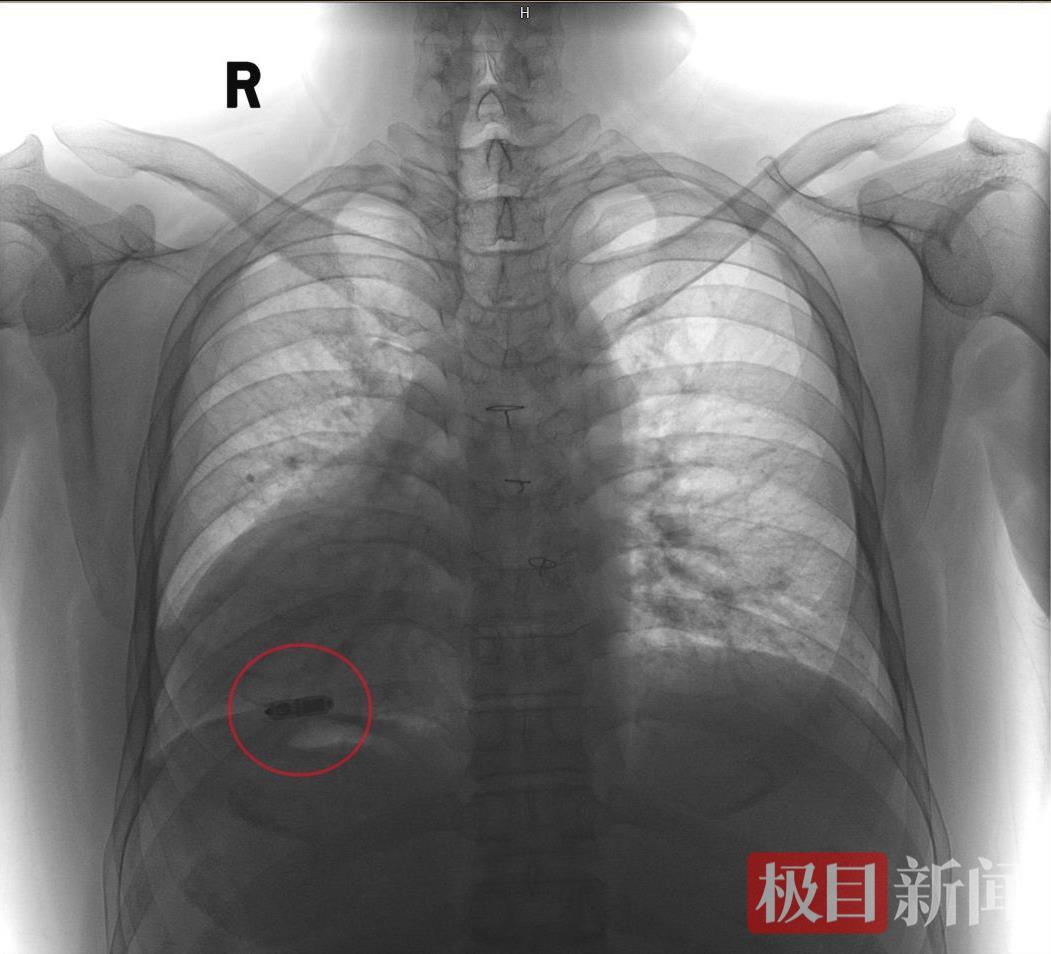

仅胶囊大小的起搏器已植入小樊心腔内

术中,韩宏伟主任通过造影剂显影发现,小樊脖子左侧的颈内静脉到上腔静脉再到右心房的这条新路是顺畅的,在历经三次尝试后,成功通过该路径将无导线起搏器送入小樊的心腔内,全程历时近2个小时。术后各项参数良好,小樊又恢复了规律且有力的心跳,术后2天就康复出院了。